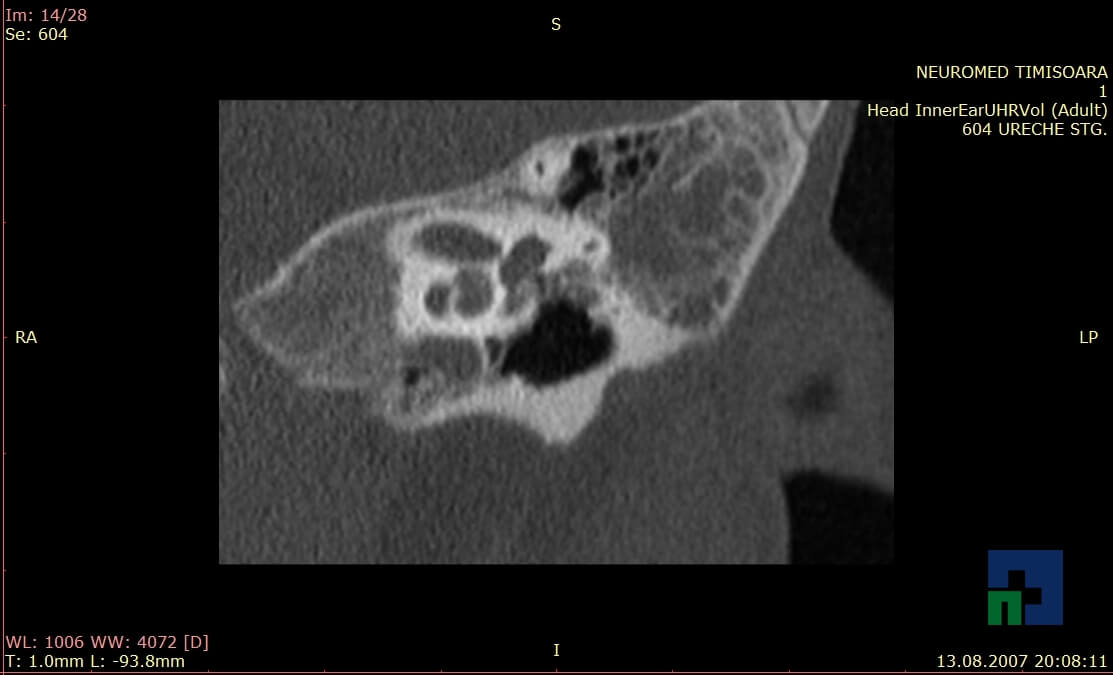

- Diagnosticul traumatismelor de bază de craniu